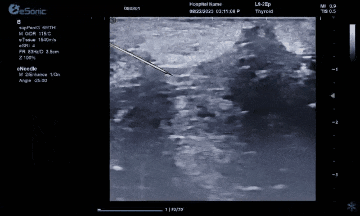

而准台式RTE弹性成像在超声介入应用中又是一大助力。操作简单、高实时性高重复性、通过颜色可直观评评估组织软硬程度。也有助于非肿块区域硬度异常的发现和评估。在穿刺中可引导穿刺到硬度较大的区域,提高穿刺阳性的成功率。

智能介入解决方案、无磁导航,可以在比较复杂的环境中,如ICU、其它床旁等场景下应用时,不会受周围机器的影响。另外,除了常规的穿刺针智能增强,支持针体增强程度调节外,智能穿刺针彩色Map技术又是利来国国际网站医疗(ESI)准台式超声的首创技术。在超声引导穿刺消融的过程中,能够增强穿刺针与组织的对比度,清晰显示针尖与针体。